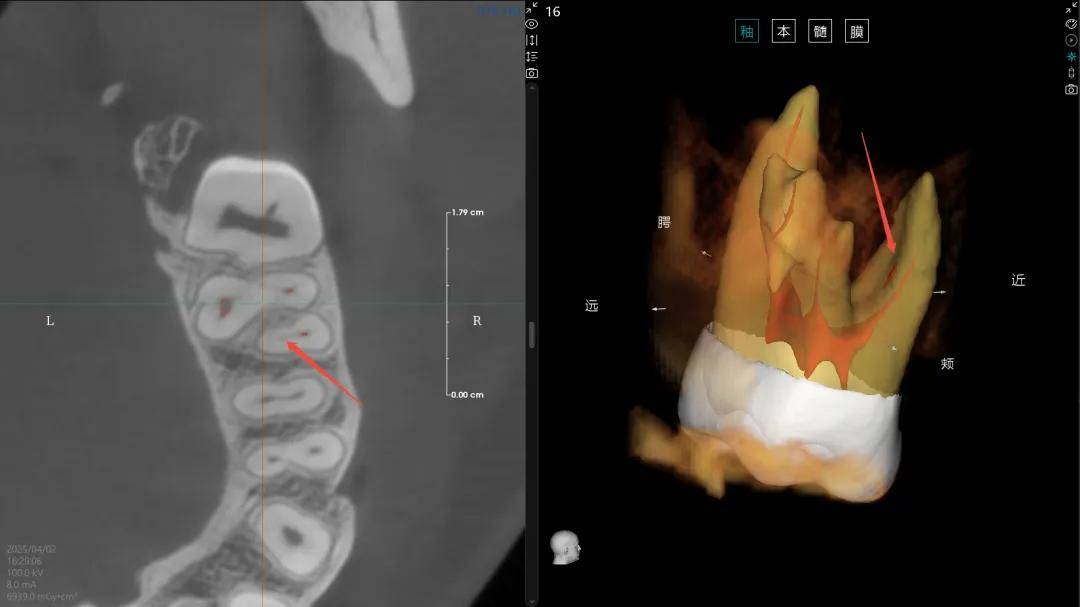

(4)“髓易诊”功能精准度与使用体验再提升,根管弯曲度支持手动/智能测量;髓腔提取算法迭代,识别准确率大幅飙升;新增牙体360°环绕观察,全方位掌控解剖细节,让根管诊疗更精准、更高效。

【▲算法优化前后MB2病例展示(优化前)】